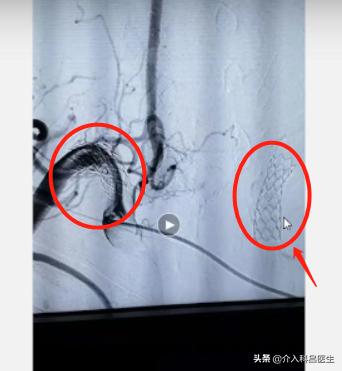

这位患者实际上是以前我们给他做的治疗。在这里边有个好像网格状的两个东西,这就是以前给他做的所下动脉的支架。当时他血管严重狭窄,我们给他放了两个支架,还都挺通畅。

这是右侧的颈内动脉,而这个地方有一个小的动脉瘤,不大但是明显的突起,并且现在形状有了改变这个动脉瘤我给大家科普过,血管的壁特别的薄,里面压力又特别高,随时有可能破裂。所以我们就和家属交谈,不行的话,我们下一步就把这个动脉瘤预防性的做一个介入栓塞治疗,把这个瘤子里边填满,血进不去它就不会再破裂出血了,这就比较安全了。